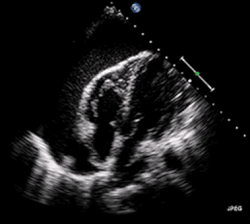

Se debe utilizar el EKG también. Taquicardia es más común por EKG. Sin embargo, se puede demostrar otras anormalidades según la causa subyacente.[20][23] Se utiliza la ecocardiografía también.[6] Produce imágenes del corazón para ayudar en el diagnóstico de los cuatro tipos de shock. Se permite evaluar varios parámetros como la función de los ventrículos y válvulas.[24] El tamaño de la vena cava inferior indica si hay aspecto de hipovolemia.[6] En choque obstructivo, la vena cava sería dilatada.[24]

La ecocardiografía también evalúa por las causas de choque obstructivo. Detecta un derrame pericárdico con facilidad.[24][25] Además, en el taponamiento cardíaco, se puede ver el colapso de las cámaras del corazón.[20] En el caso de embolia pulmonar masiva o submasiva, se vería el ventrículo derecho dilatado. Otros signos ecocardiográficos son coágulos en el corazón derecho y el movimiento paradójico del tabique interventricular. Al otro lado, la angiografía por TC es la prueba preferida para diagnosticar la embolia pulmonar.[12]